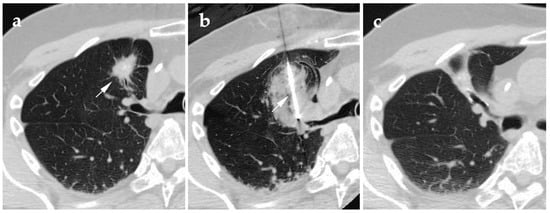

4.2. Radiofrequency Ablation